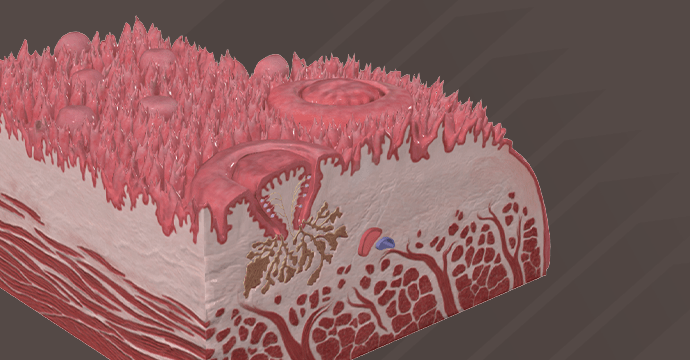

Take your understanding of human anatomy to the next level. Our comprehensive resources combine detailed information and stunning illustrations!

Enhance your studies for a truly dynamic learning experience. Explore interactive anatomy models from Complete Anatomy. Start mastering anatomy today with our free anatomy flashcards designed for quick review on the go.